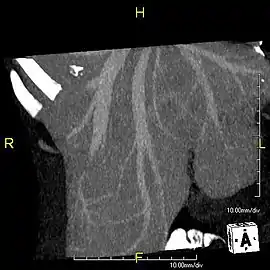

Left lobe liver tumor

The liver is a vital organ and supports almost every other organ in the body. Because of its strategic location and multidimensional functions, the liver is prone to many diseases.[52] The bare area of the liver is a site that is vulnerable to the passing of infection from the abdominal cavity to the thoracic cavity. Liver diseases may be diagnosed by liver function tests–blood tests that can identify various markers. For example, acute-phase reactants are produced by the liver in response to injury or inflammation.